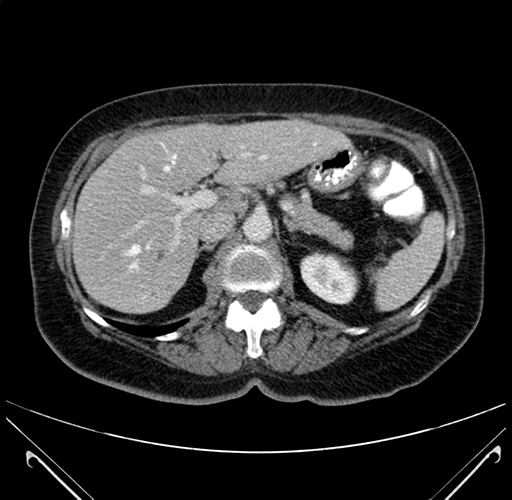

Axial Venous